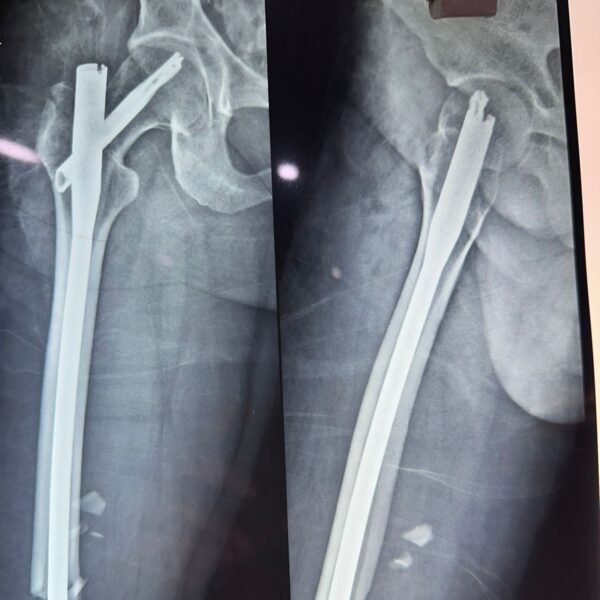

Moments That Mark Meaningful Recovery

Witness real patient transformations at The Ortho Clinic through images that reflect successful treatments and restored mobility.